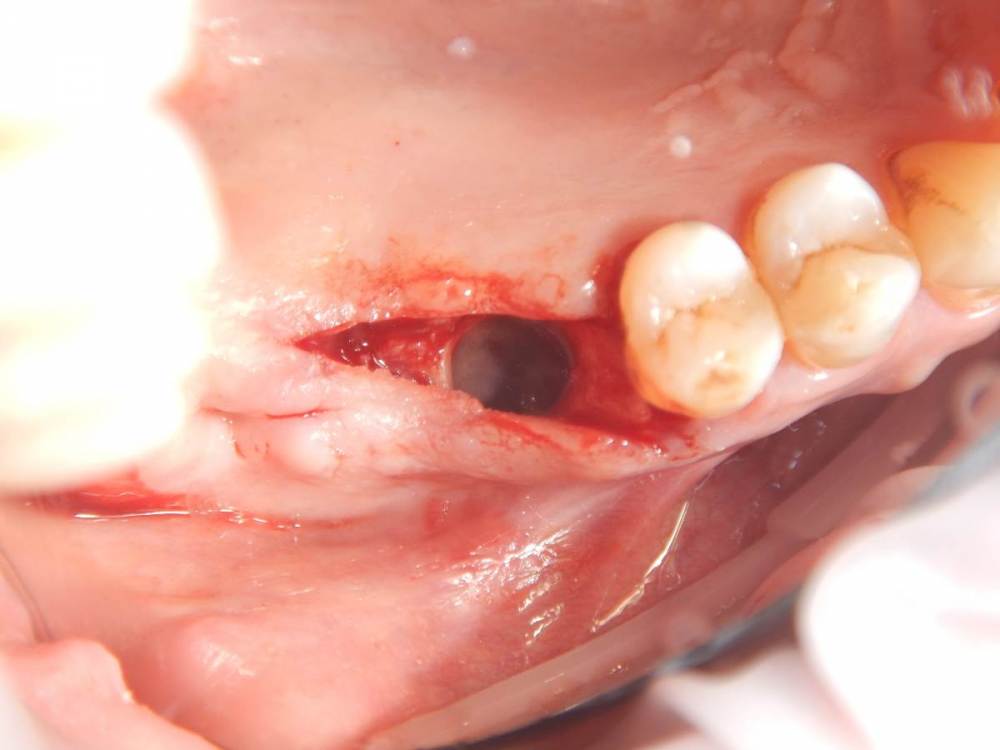

annda Опубликовано 11 июня, 2021 Поделиться Опубликовано 11 июня, 2021 (изменено) Ничего не беспокоит.Зубы удалены лет 15 назад Изменено 11 июня, 2021 пользователем annda 1 Ссылка на комментарий

Карен Аванесов Опубликовано 11 июня, 2021 Поделиться Опубликовано 11 июня, 2021 Анна здравствуйте. Версий много, вскрытие покажет, главное нет признаков воспаление, в любом случае интересный клинический случай под минимальное вмешательство, обязательно покажите развязку. 1 Ссылка на комментарий

Astronaft Опубликовано 11 июня, 2021 Поделиться Опубликовано 11 июня, 2021 Радиография была один в один с вашим случаем. Результат биопсии: рецидуальная киста с кристаллами холестерина. Но конечно может быть что-нибудь другое. 4 Ссылка на комментарий

annda Опубликовано 12 июня, 2021 Автор Поделиться Опубликовано 12 июня, 2021 (изменено) Спасибо всем. Вмешательства не было, кроме удаления. Я так понимаю, тактика заключается в доступе и банально кюретаже? Графт по убеждениям, дефект все одно получается практически четырехстеночный... Главное, не наджабить кортикалку ГП. Я так понимаю, процесс все же из пазухи, был с зубами связан? Изменено 12 июня, 2021 пользователем annda Ссылка на комментарий

Astronaft Опубликовано 12 июня, 2021 Поделиться Опубликовано 12 июня, 2021 (изменено) В моем случае процесс одонтогенный. Киста это остаток после удаления зуба. В вашем случае не должен быть из пазухи. Да - там есть истончение кортикальной пластины в одном месте, но вроде как без инвагинации. Границы везде четкие, т.е. процесс доброкачественный. Из пазухи в кость можно проникнуть только инвазивно. Лизис, а не раздвигание. Карцинома - границы были бы другие. Т.е. процесс либо происходит из самой кости, или одонтогенный. Изменено 12 июня, 2021 пользователем Astronaft 1 Ссылка на комментарий